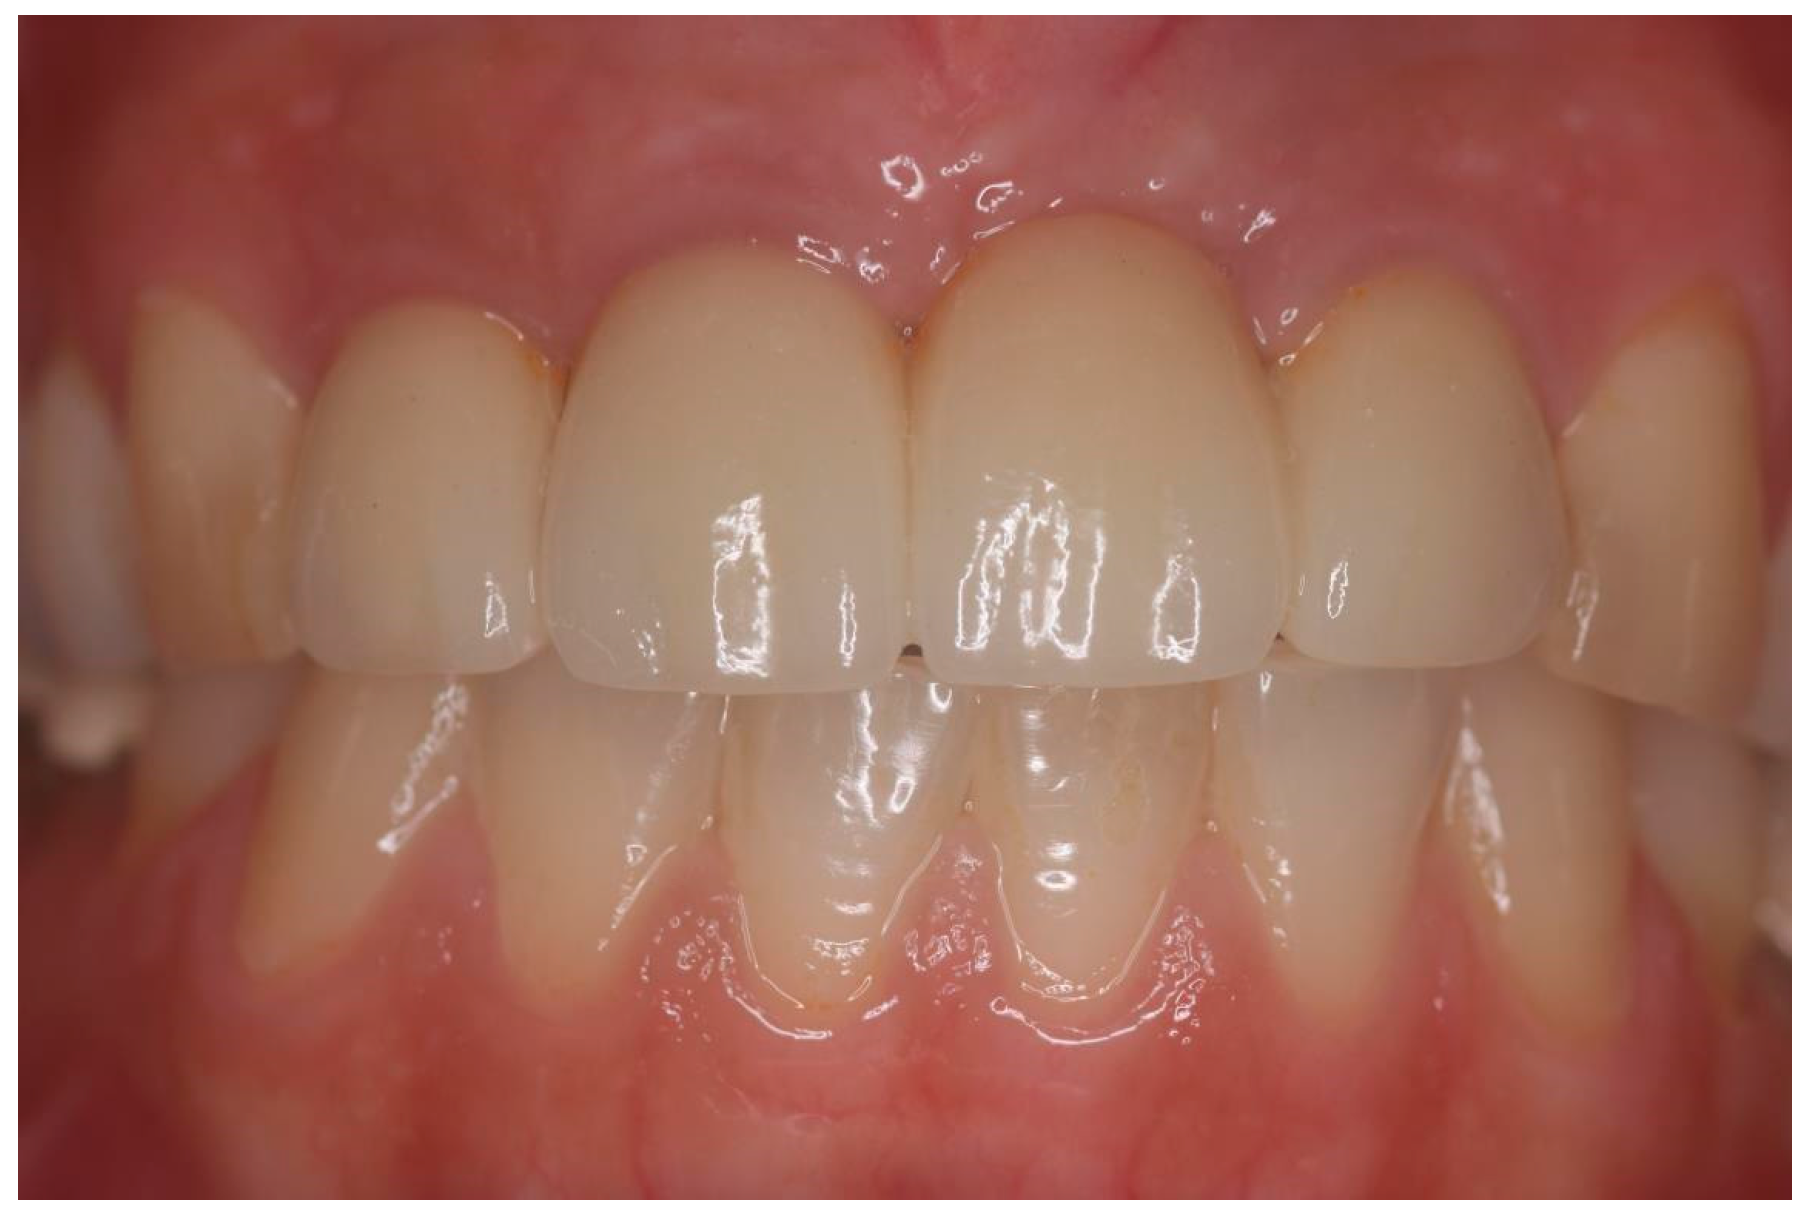

Figure 6.

Sixty-year-old nonsmoking woman with hopeless 12–22 teeth due to severe carious lesions (patient #29).

Figure 8.

Fixed partial zirconia bridges (patient #29).